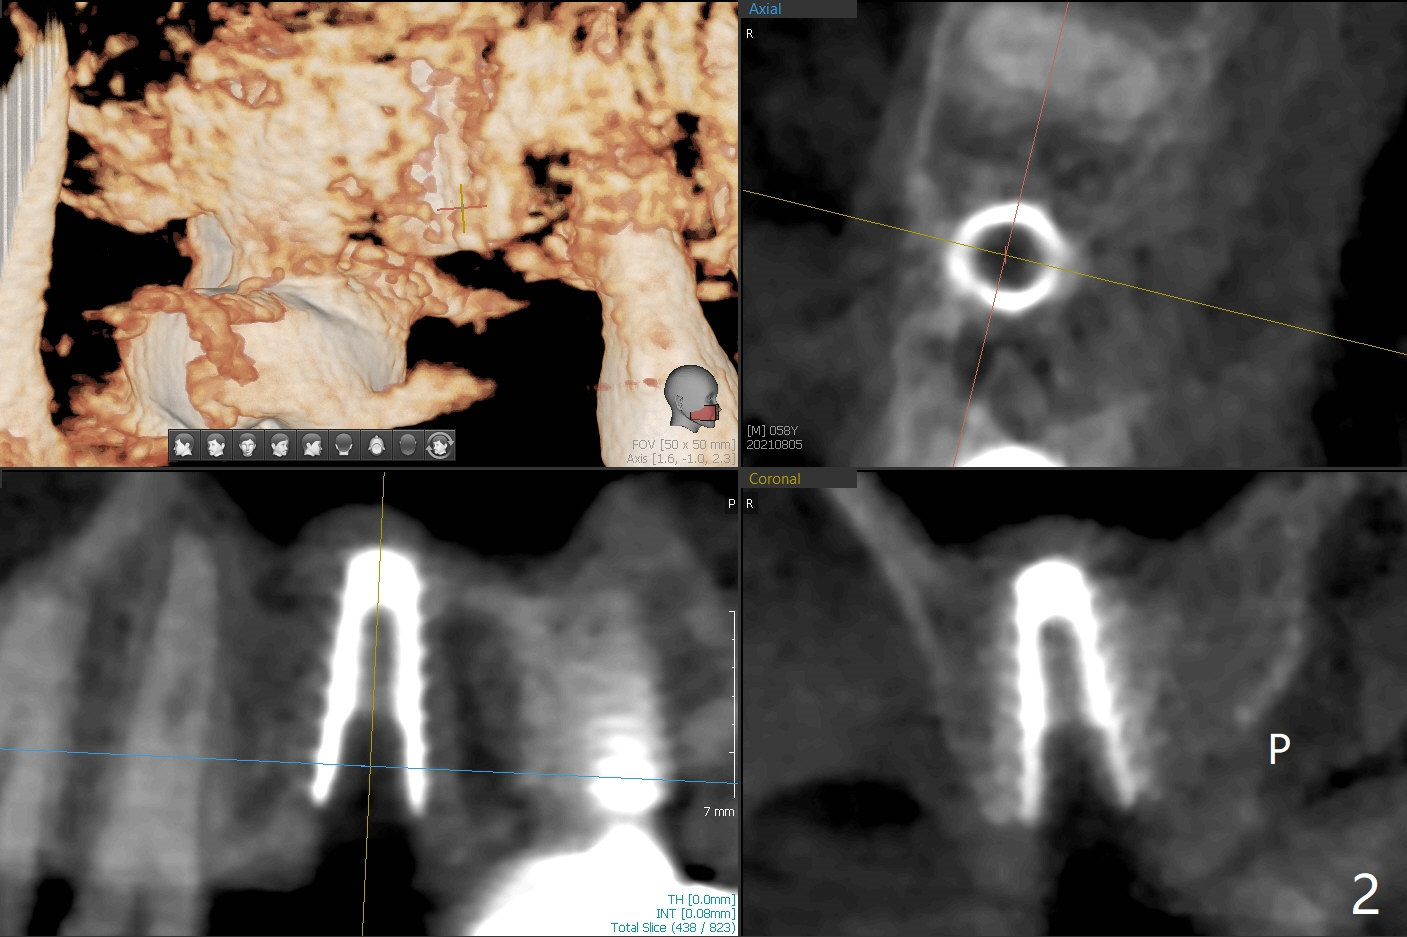

58岁男3号牙位点保存后11个月回来种植,在导板指引下,完成钻洞(3.5x7.3毫米钻头),窦底好像没有破裂,但是仍放置粘性骨粉,使用4x8.5毫米报废植体提升,没有成功。使用2.2x8.5和3.0x8.5毫米钻头,加放骨粉,再次旋入报废植体(大约7.3毫米,图一),骨粉进入上颌窦(*)。使用3.5x8.5毫米钻头后,放置骨粉,植入正式4.5x9毫米(图二,~15Ncm),由于骨扩张,临床检查也证明腭侧(P)不需要植骨,植体周围骨质密度增加。使用5.5毫米Profile钻头(图三:<)后,放置4.5x3毫米愈合基台,PRF膜插入后者和牙龈之间。